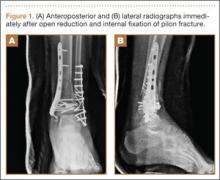

A 23-year-old man sustained a left grade III open pilon fracture after a fall off a cherry picker. He was initially treated with irrigation and débridement of the open anteromedial wound, wound closure, application of external fixation, and open reduction and internal fixation (ORIF) of the concomitant comminuted fibular fracture. Operative fixation of the pilon was performed 3 weeks after injury, once skin and soft tissues were in acceptable condition (Figure 1). Skin closure was performed with 2-0 Vicryl sutures (Ethicon, Inc, Somerville, New Jersey) followed by 3-0 nylon skin sutures and No. 2 nylon retention sutures to reduce tension at the incision.